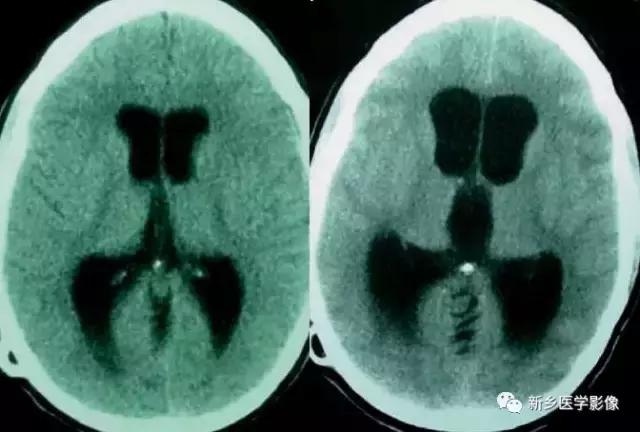

(1)前脑无裂畸形: (holoprosencephaly)是指一系列位于中线程度不同的畸形,累及大脑、面部、脑于和小脑.前脑未能够分开,呈不全性或完全性,端脑和间脑无法区分。根据脑及面部畸形程度将其分为无叶型、半叶型和单叶型。

无叶型前脑无裂畸形最严重.端脑半球间没有裂隙,呈马蹄形或新月形扩大的单脑室跨越中线,与背侧囊交通。丘脑互相融合,面部畸形从两眼距离过近到独眼畸形.往往死于胎儿或新生儿期。

半叶型前脑无裂畸形在前脑可见部分裂隙. 形成不同发育程度的大脑纵裂及大脑镰。两侧大脑半球在前部未完全分开,但枕叶和 双侧侧脑室体部分离,丘脑分开不完全。三脑室和海马发育不全,胼胝体仅可见到压部,而其他部分缺如.额叶和基底节前部分辨不清。临床表现有两眼距离过近.及唇裂、腭裂等面部畸形,侧脑室呈单一性.且明显扩大。

单叶型前脑无裂畸形与正常发育脑仅有些很小的区别.如透明隔缺如或双侧额叶不完全分开。